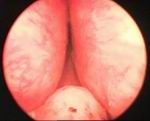

Prostatic enlargement is a comman problem is old age. By TURP nearly all patient who requires surgery for prostate can be treated successfully without any incision. Under anesthesia per urethral scope is inserted & under vision prostate is resected. Patient requires 2 to 4 days hospitalization & 1 week rest. Usually patient does not requires blood transfusion & patient can tolerate endoscopic surgery very well without risk of incontinance of urine.